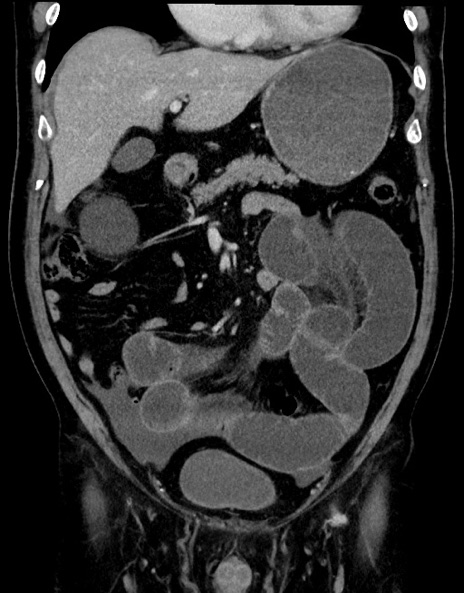

横断像

【症例】70歳代男性

【主訴】腹痛

【現病歴】今朝から腹痛あり。全体的に痛い。特に左上の方。排ガスが今日はない。冷や汗が出る。

【既往歴】直腸癌術後

【身体所見】左側腹部〜上腹部に圧痛あり。腹膜刺激症状明らかなではない。軽度反跳痛。左下腹部に術後瘢痕あり。

【データ】WBC 7700、CRP 0.02